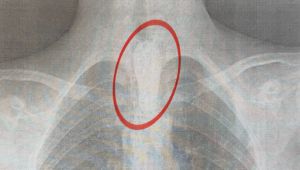

На Львівщині у підлітка в стравоході застряг шашлик. Як рятувалиПід час вечері він з'їв великий шматок шашлика, який застряг у стравоході.

Медицина